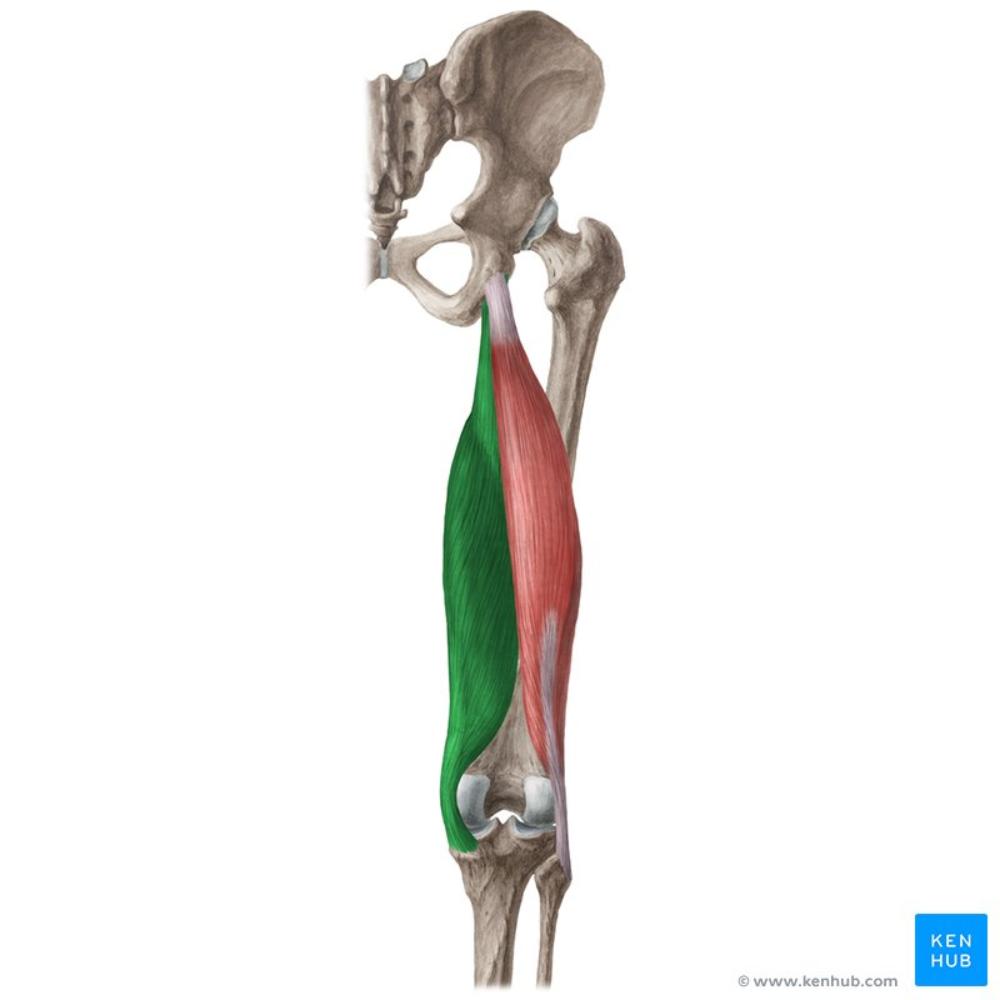

semitendinosus

O: ischial tuberosity

I: medial, superior tibia

A: flexes knee, extends thigh

N: tibial nerve